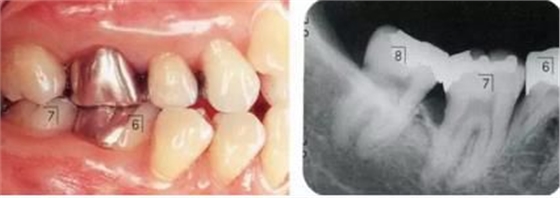

▲圖9-1,2

▲圖9-1 預(yù)定進(jìn)行正畸治療的患者,下頜磨牙區(qū)的右下6,7牙根接近,并在右下7遠(yuǎn)中存在垂直性骨組織缺損。對(duì)牙體狀況、牙周組織、咬合情況進(jìn)行診斷后制定出的治療方案為:將右下6拔除,對(duì)右下7遠(yuǎn)中的骨組織缺失進(jìn)行再生療法。

▲圖9-2 同部位X光片。右下6遠(yuǎn)中存在牙根接近,較深的骨組織缺損以及II度根分叉病變,所以將其拔除。

▲圖9-3

拔牙后1周的狀態(tài)。愈合后,預(yù)定進(jìn)行正畸治療穩(wěn)定牙列。